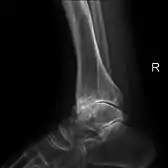

هشاشة العظام الشديدة وهشاشة العظام في المفصل الرسغي

هشاشة العظام الابتدائية في الركبة اليسرى. يلاحظ وجود عظيمات، وضييق المساحة داخل المفصل (السهم)، وزيادة كثافة العظام تحت الغضروف (السهم).